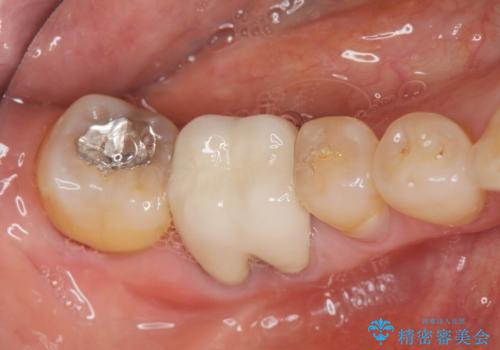

- 右下奥歯からの排膿、痛みの改善を希望され来院されました。

薄い歯質の歯牙に過大な負荷がかかり亀裂を生じ大臼歯分岐部に大きな骨吸収を認め、抜歯を余儀なくされる状態です。

抜歯を行ったのち前後の歯に軽度の動揺があるため、インプラントではなくブリッジによる補綴処置を行い機能回復を行いますが、近心傾斜した第2大臼歯をマイクロインプラントを用いた小矯正を行うことで歯軸方向を改善し、神経を温存した状態でブリッジ製作できるよう前処置を行います。